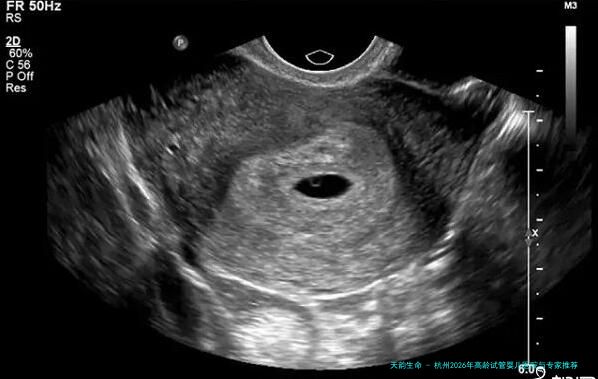

起首,让我们了解一下试管婴儿技术。试管婴儿技术是一种人类辅助生殖技术,帮助不孕不育夫妻完成生育梦想。在试管婴儿技术中,医生会从女性身体内拿出卵子,与男性精子结合变成受精卵,然后将受孕卵移植女性子宫内,使其发育成胎儿。